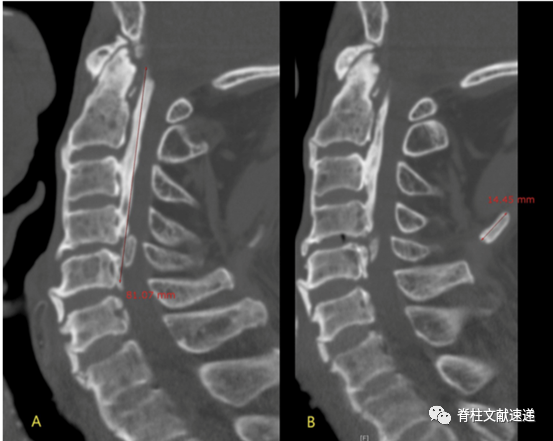

该文献也由姜建元教授团队发表。文献进一步指出:

1.局灶型项韧带骨化的位置往往位于椎管最狭窄的水平;

2. 局灶型项韧带骨化的位置与椎体骨赘的大小有关;

3. 局灶型项韧带骨化的位置与椎间盘退变的程度有关。如下图所示:C5/6颈椎不稳、骨质增生,项韧带骨化发生于C5和C6棘突之间。